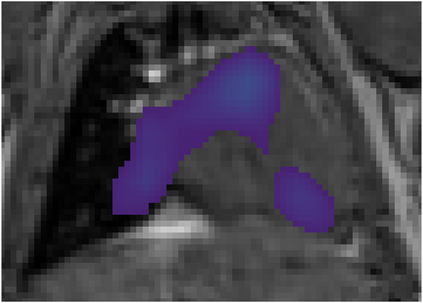

Various imaging modalities allow for time-dependent image reconstructions from measurements where its acquisition also has a time-dependent nature. Magnetic particle imaging (MPI) falls into this class of imaging modalities and it thus also provides a dynamic inverse problem. Without proper consideration of the dynamic behavior, motion artifacts in the reconstruction become an issue. More sophisticated methods need to be developed and applied to the reconstruction of the time-dependent sequences of images. In this context, we investigate the incorporation of motion priors in terms of certain flow-parameter-dependent PDEs in the reconstruction process of time-dependent 3D images in magnetic particle imaging. The present work comprises the method development for a general 3D+time setting for time-dependent linear forward operators, analytical investigation of necessary properties in the MPI forward operator, modeling aspects in dynamic MPI, and extensive numerical experiments on 3D+time imaging including simulated data as well as measurements from a rotation phantom and in-vivo data from a mouse.